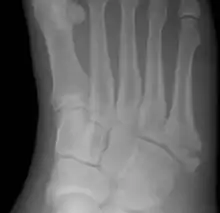

Jones fracture

A Jones fracture is a broken bone in a specific part of the fifth metatarsal of the foot between the base and middle part[8] that is known for its high rate of delayed healing or nonunion.[4] It results in pain near the midportion of the foot on the outside.[2] There may also be bruising and difficulty walking.[3] Onset is generally sudden.[4]

| Jones fracture as seen on Xray | |